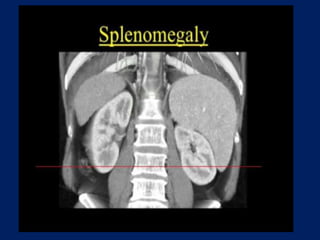

This document discusses imaging of the spleen and summarizes various congenital anomalies and pathologies that can affect the spleen. Some common congenital anomalies mentioned include accessory spleens, asplenia, polysplenia, and splenic fusions. Acquired conditions like repeated infarctions, infiltration, tumors, and cysts can also cause splenomegaly or functional asplenia. Wandering spleen is discussed as a rare congenital anomaly where the spleen lacks attachments and is mobile within the abdomen. Various grades of splenic lacerations and examples of splenic imaging findings are also briefly summarized.